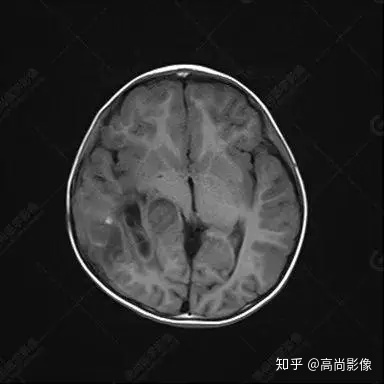

右側(cè)顳葉腫瘤切除術(shù)后(具體不詳):右側(cè)顳部骨質(zhì)不連續(xù)呈術(shù)后改變,右側(cè)顳葉術(shù)區(qū)見片狀長(zhǎng)T1長(zhǎng)T2信號(hào)影,F(xiàn)LAIR呈低信號(hào);術(shù)區(qū)后方右側(cè)顳枕葉見一巨大占位性病變影,邊界欠清,大小約6.2×5.8×4.3cm(前后×左右×上下),信號(hào)不均勻,T1WI呈等稍低信號(hào)間雜少許高信號(hào),T2WI呈高稍低混雜信號(hào),DWI示部分病灶彌散受限,相應(yīng)ADC圖減低,磁敏感序列見部分呈極低信號(hào),增強(qiáng)掃描可見明顯不均勻強(qiáng)化,鄰近硬腦膜及小腦幕增厚并明顯強(qiáng)化;另延髓右前方及右側(cè)橋小腦角區(qū)見一不規(guī)則形異常信號(hào)影,大小約3.2×1.3×3.7cm(左右×前后×上下),呈長(zhǎng)T1稍長(zhǎng)T2信號(hào),F(xiàn)LAIR呈等信號(hào),DWI未見受限,增強(qiáng)后明顯均勻強(qiáng)化,鄰近腦膜明顯強(qiáng)化。鄰近腦實(shí)質(zhì)及右側(cè)顳角明顯受壓;左側(cè)大腦半球未見局灶性信號(hào)異常,中線結(jié)構(gòu)稍左移。

右側(cè)顳葉腫瘤切除術(shù)后:現(xiàn)術(shù)區(qū)后方右側(cè)顳枕葉及延髓右前方占位,右側(cè)顳枕部硬腦膜及小腦幕明顯強(qiáng)化,結(jié)合既往影像資料,考慮為胚胎源性惡性腫瘤,如非典型畸胎樣/橫紋肌樣瘤(AT/RT)或原始神經(jīng)外胚層腫瘤(PNET)。

非典型畸胎樣/橫紋肌樣瘤(AT/RT) 是一種高度惡性中樞神經(jīng)系統(tǒng)腫瘤,臨床罕見,臨床表現(xiàn)無(wú)特異性,好發(fā)于 5 歲以下兒童,尤以 3 歲以下多見,在兒童原發(fā)性中樞神經(jīng)系統(tǒng)(CNS)腫瘤中占 1%~3%。該腫瘤體積一般較大,幕上大于幕下,有明顯的占位效應(yīng)。該腫瘤成分復(fù)雜,囊變、出血、壞死常見。因此 AT/RT信號(hào)混雜,囊性部分呈 T1WI低、T2WI高信號(hào),增強(qiáng)后不強(qiáng)化;若瘤體出血,囊內(nèi)可見T1WI稍高信號(hào)、T2WI低信號(hào),實(shí)性部分在 T1WI上呈混雜等、低信號(hào),在T2WI 及 T2-FLAIR上呈混雜等高信號(hào),增強(qiáng)掃描后大部分呈環(huán)形條帶樣明顯強(qiáng)化,中心壞死區(qū)不強(qiáng)化。另外,該腫瘤實(shí)性成分在DWI上呈高信號(hào),說(shuō)明腫瘤細(xì)胞核密集,水分子擴(kuò)散明顯受限,提示該腫瘤惡性程度高,容易復(fù)發(fā)及轉(zhuǎn)移。